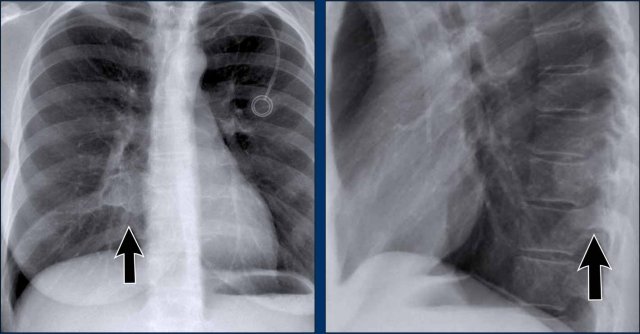

Case Example: Subtle Signs of Congestive Heart Failure

Begin by reviewing these current chest radiographs.

Based solely on these images, one might suspect congestive heart failure (CHF), though the findings are subtle.

Now review the previous study…

Scrolling between the current and prior films significantly increases diagnostic confidence in your diagnosis of congestive heart failure.

Key comparative findings include:

• Cardiac size: Slightly increased compared to the previous study; however, cardiomegaly was already present.

• Pulmonary vasculature: Mild vascular engorgement suggesting elevated pulmonary venous pressure.

• Interstitial markings: Subtle signs of interstitial edema .

• Pleural effusions: Bilateral small effusions, with subtle changes in the inferoposterior borders of the lower lobes, suggesting fluid accumulation.